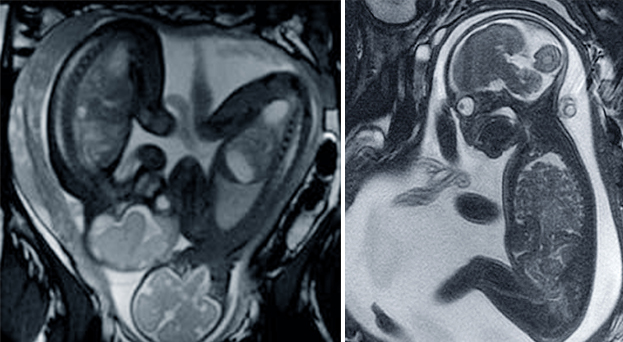

Resonancia magnética gemelar e individual.

La resonancia magnética fetal es muy práctica para el estudio intraútero del desarrollo cerebral debido a que, gracias a su adquisición rápida de imagen, hace biometría cerebral y análisis de desarrollo de los giros corticales, la mielinización y la migración neuronal. Es superior a la ecografía en el estudio de la sustancia blanca del cerebro y, gracias a su potencia de visualización, diagnostica lesiones isquémicas agudas fetales.

Aunque la ecografía es el método de estudio rutinario del feto, en ocasiones es necesario obtener imágenes de mayor calidad para la detección de alteraciones sutiles o complejas, para la preparación de cirugías fetales o para manejos especiales posnatales tras el parto. La resonancia magnética ayuda a obtener imágenes excelentes con un campo de visión mayor o en el que se aprecien mejor las diferencias entre tejidos. "En estas ocasiones la resonancia magnética fetal es la mejor opción", afirma el doctor Recio, quien opina que las imágenes obtenidas son muy útiles para valorar patologías cerebrales durante el embarazo, para alteraciones detectadas por ecografía en las que se tiene que comprobar su grado de afectación, para casos de obesidad materna, posición inadecuada del feto o escasa cantidad de líquido amniótico y para los fetos que presentan un riesgo elevado de anomalías cerebrales, como infecciones fetales o daño isquémico.